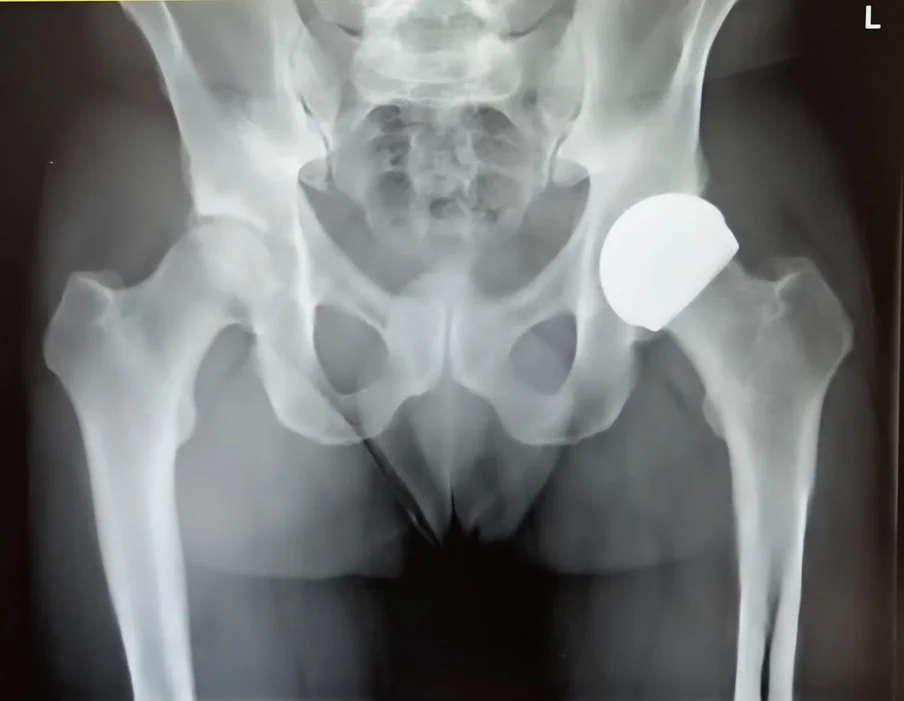

Surgical Images & X-rays

Hip resurfacing is a surgical procedure that treats hip arthritis while preserving significantly more of your natural bone than a traditional total hip replacement. Instead of removing the entire femoral head (the ball of the hip joint), it is reshaped and capped with a smooth metal or ceramic covering. The damaged hip socket is also resurfaced with a matching shell.

A ceramic-on-ceramic resurfacing implant suitable for both male and female patients. Eliminates metal ion concerns associated with traditional resurfacing. Uses hybrid fixation with cement in the femoral component.